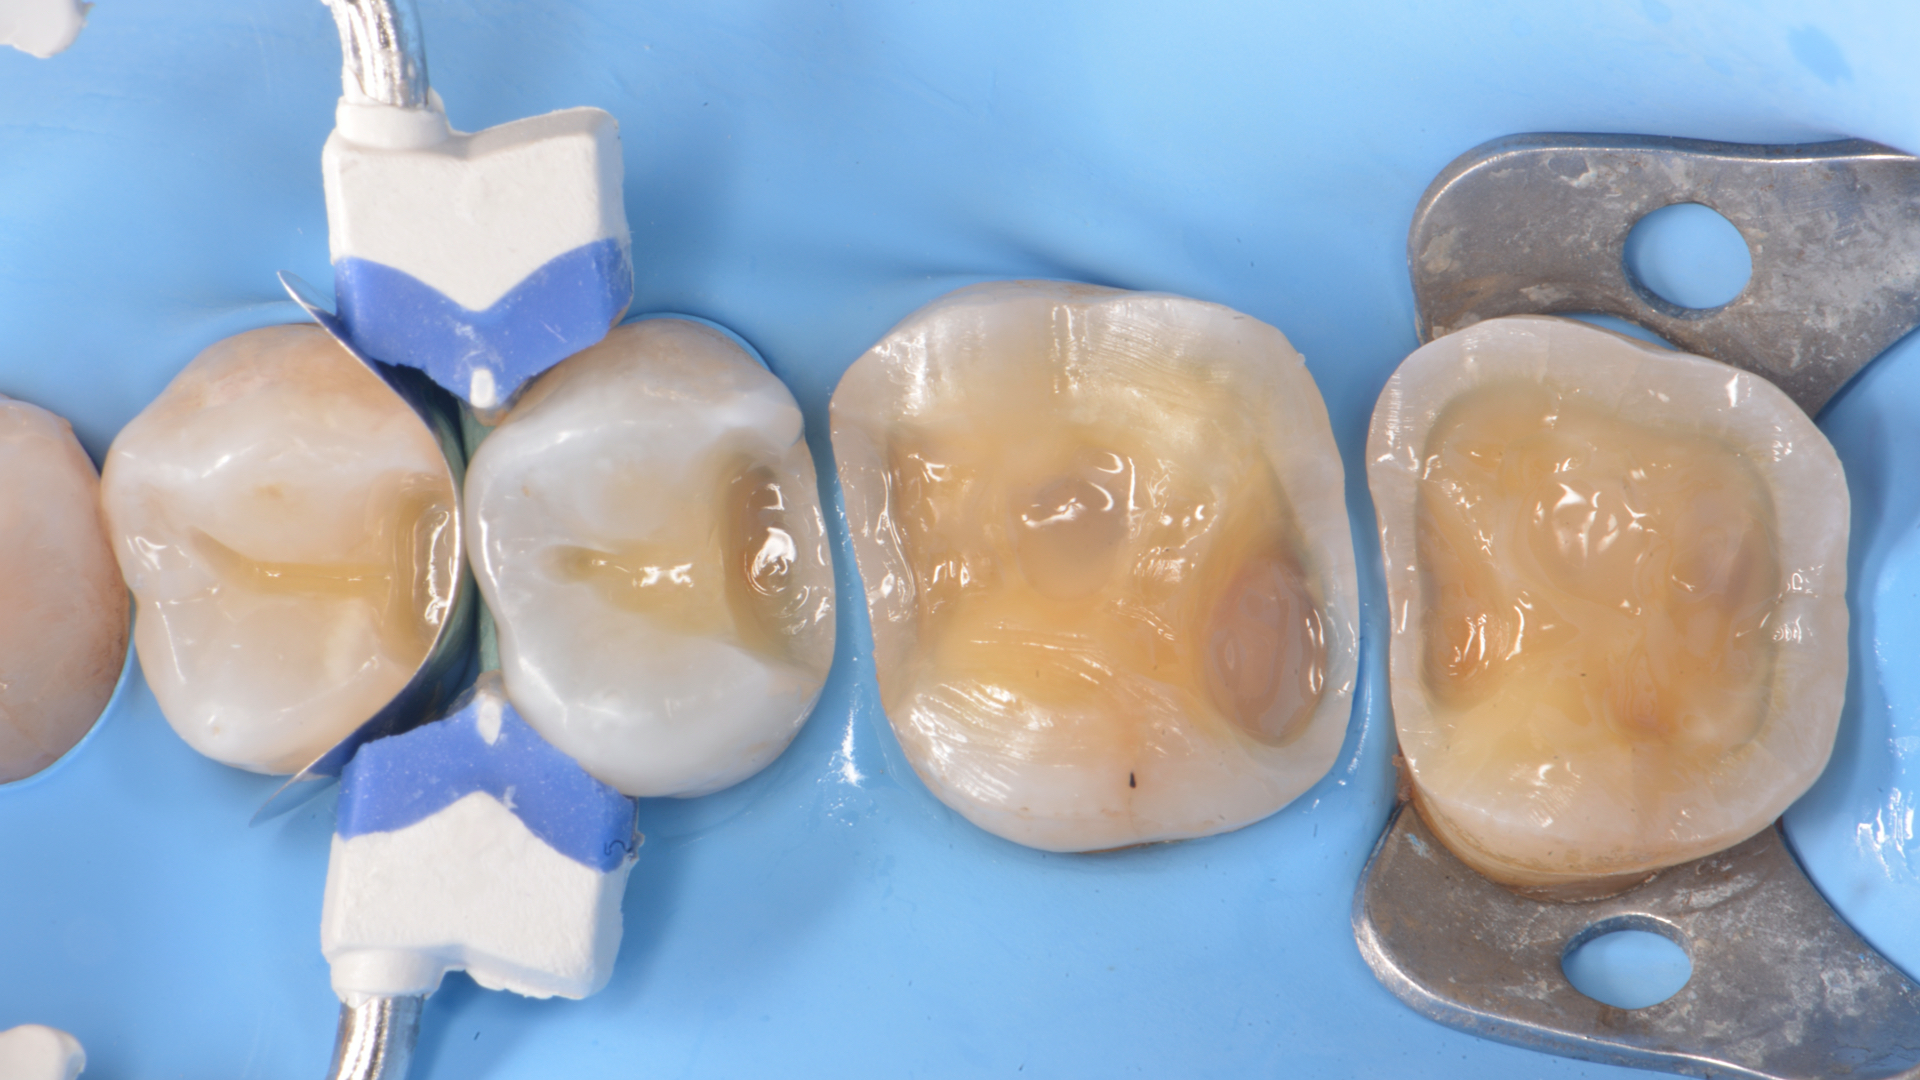

Il paziente si è presentato alla nostra osservazione lamentando fastidi in masticazione e sensibilità termica nell’arcata superiore destra.  Dopo  esame  clinico  e  radiografico  si  sono  evidenziate lesioni cariose a carico degli elementi 1.7-1.6-1.5.-1.4 Si è optato per un restauro diretto in composito con approcci minimamente invasivo negli elementi 1.4 ed 1.5 . A carico degli elementi 1.7 e 1.6 sono stati invece programmati restauri indiretti in composito ibrido a ricopertura cuspidale. Questa scelta è stata presa dopo una accurata valutazione biomeccanica delle strutture residue.

Dopo  avere  eseguito  i  restauri diretti tramite l’utilizzo del sistema sezionale  Garrison  Composi-tight 3D Fusion sono stati preparati gli elementi  1.7  e  1.6.  L’impronta  è stata rilevata con tecnica monofase bicomponente.  Al  successivo appuntamento, previo isolamento del  campo  operatorio  con  diga di  gomma,  i  manufatti  sono stati  cementati  con  composito preriscaldato.  In  questo  caso l’utilizzo  di  tale  composito  ha facilitato  le  fasi  di  rimozione  del cemento in eccesso a causa della diversa opacità tra prima e dopo la polimerizzazione . Fasi di rifinitura,lucidatura e brillantura sono state eseguite  prima  della  rimozione della  diga.  Minimi  aggiustamenti occlusali sono stati necessari.

5

6

Fig.5 Ricostruzione parete distale 1.5 (Garrison Composi-tight 3D Fusion System)Fig.6  Restauri 1.4 ed 1.5 completati.